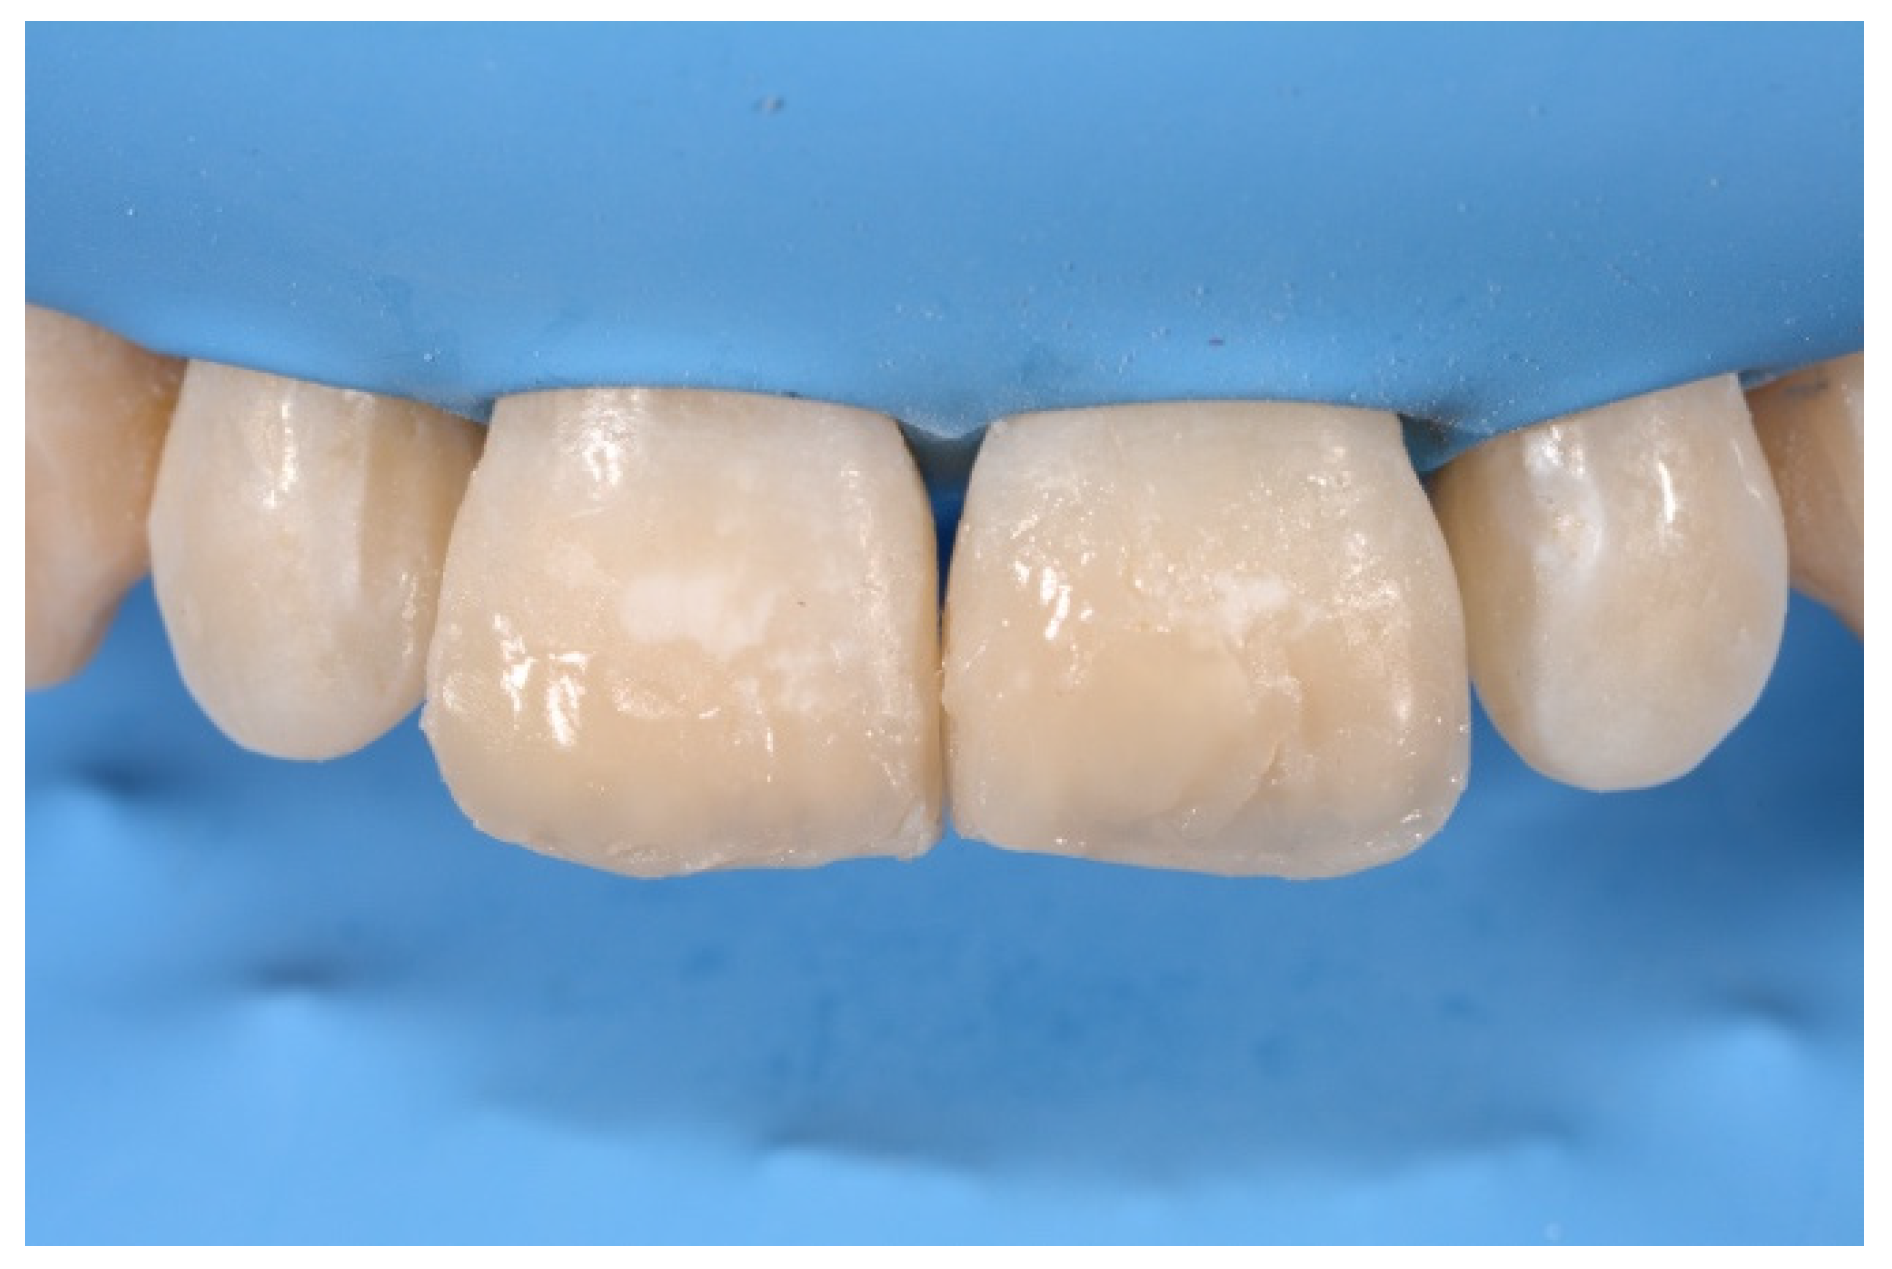

2. Case Presentation

- Molding palatal wall and incisal margin;

- Building interproximal walls with matrices;

- Layering free-hand buccal surface.